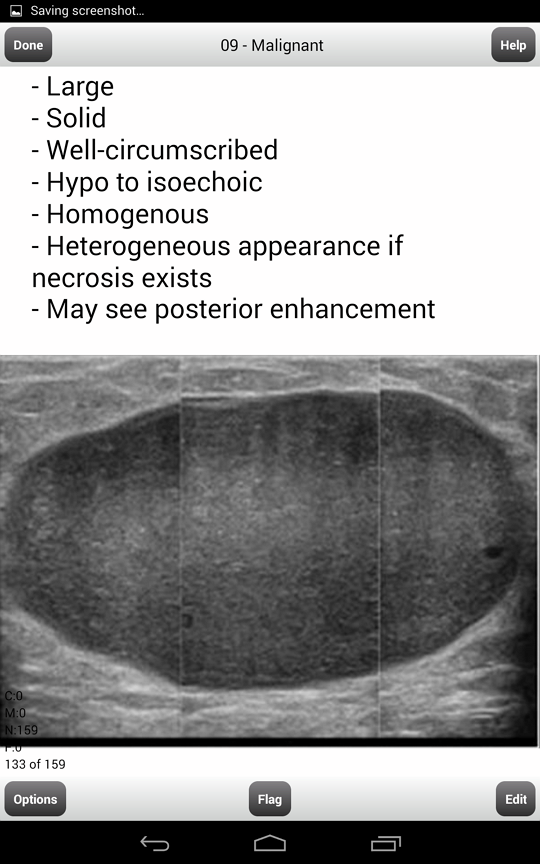

Radiology Quiz Bilateral Breast Masses Alec Chau, MD, A. Pat Romilly, MD, — Selected image from breast ultrasound revealing subcentimeter, hypoechoic, solid masses corresponding to those seen mammographically. R CC L CC 1A R MLO L MLO 1B ... Content Retrieval